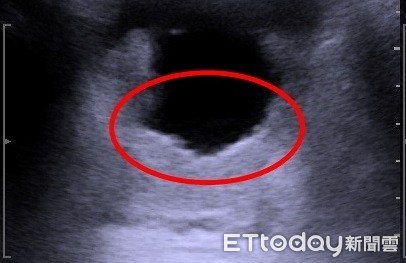

▲攝護腺肥大經過雷射手術後超音波影像。(圖/亞大醫院提供)

蕭子玄指出,時序邁入秋冬,出現上述症狀的患者也隨之增加,尤其天氣轉涼,「想尿卻尿不出來」的情況會更加嚴重,其中以50歲以上男性最為明顯。一般正常攝護腺大小約20克,該患者的攝護腺竟約80克,造成膀胱出口阻力增加,削弱肌肉收縮力量。若同時有膀胱過動的問題,就會出現頻尿又尿不乾淨的症狀。

另有部份的病人,則是攝護腺過大凸到膀胱裡,長期地刺激膀胱收縮。此時若吃抑制膀胱收縮的藥物,反倒會使患者尿不出來,造成尿液滯留,甚至引發泌尿道感染問題,故須先解決攝護腺肥大的問題,再透過抗頻尿藥物改善頻尿的症狀。

▲醫師提醒,攝護腺過大凸到膀胱裡,會長期地刺激膀胱收縮。(圖/亞大醫院提供)